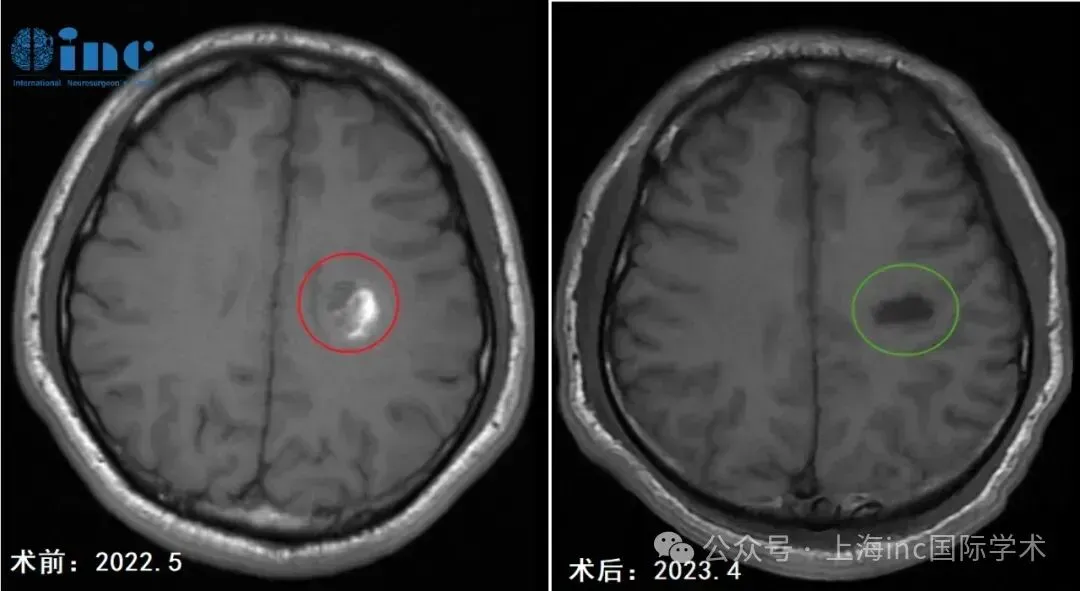

2023年4月,检查MRI影像

几小时的持续奋战,在术中导航和神经电生理监测的双重护航下,巴教授顺利安全为阿勇全切半卵圆中心海绵状血管瘤。

术前术后对比